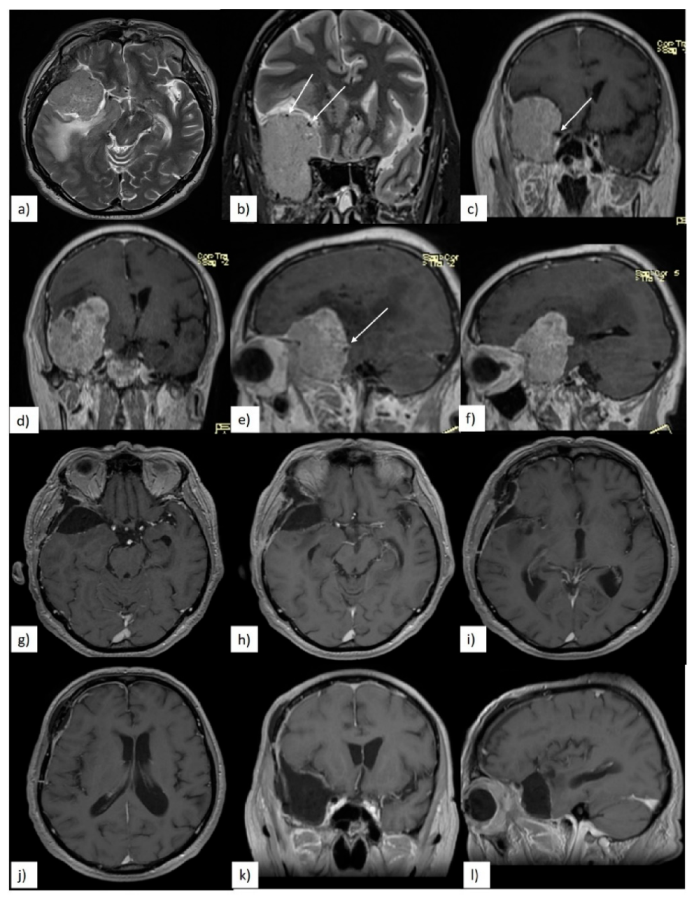

3.2. Preoperative Clinical and Radiological Data

3.3. Quality of Resection

3.4. Postoperative Clinical Evolution and Follow-up